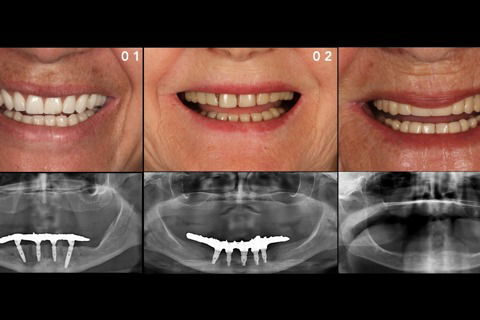

Sorriso final

Foto 17 Sorriso final